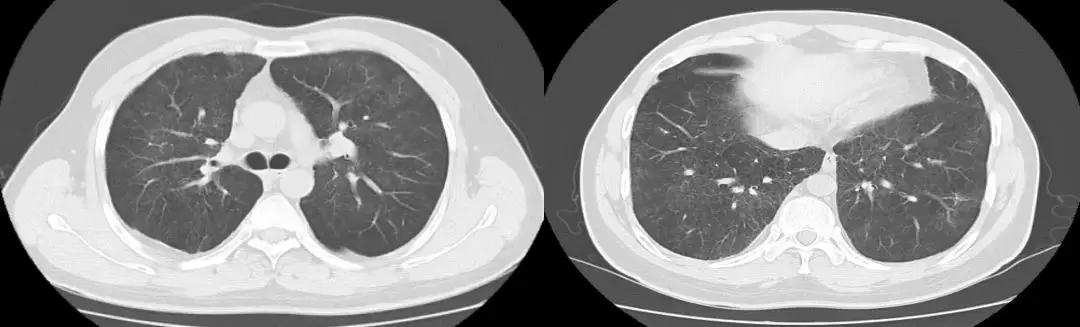

于北京协和医院查相关检查,如下图:

后给予强的松50mg 3月余。

复查胸部CT(2018-07-12):

左肺炎症较前好转,但肺部弥漫性病变较前变化不大。